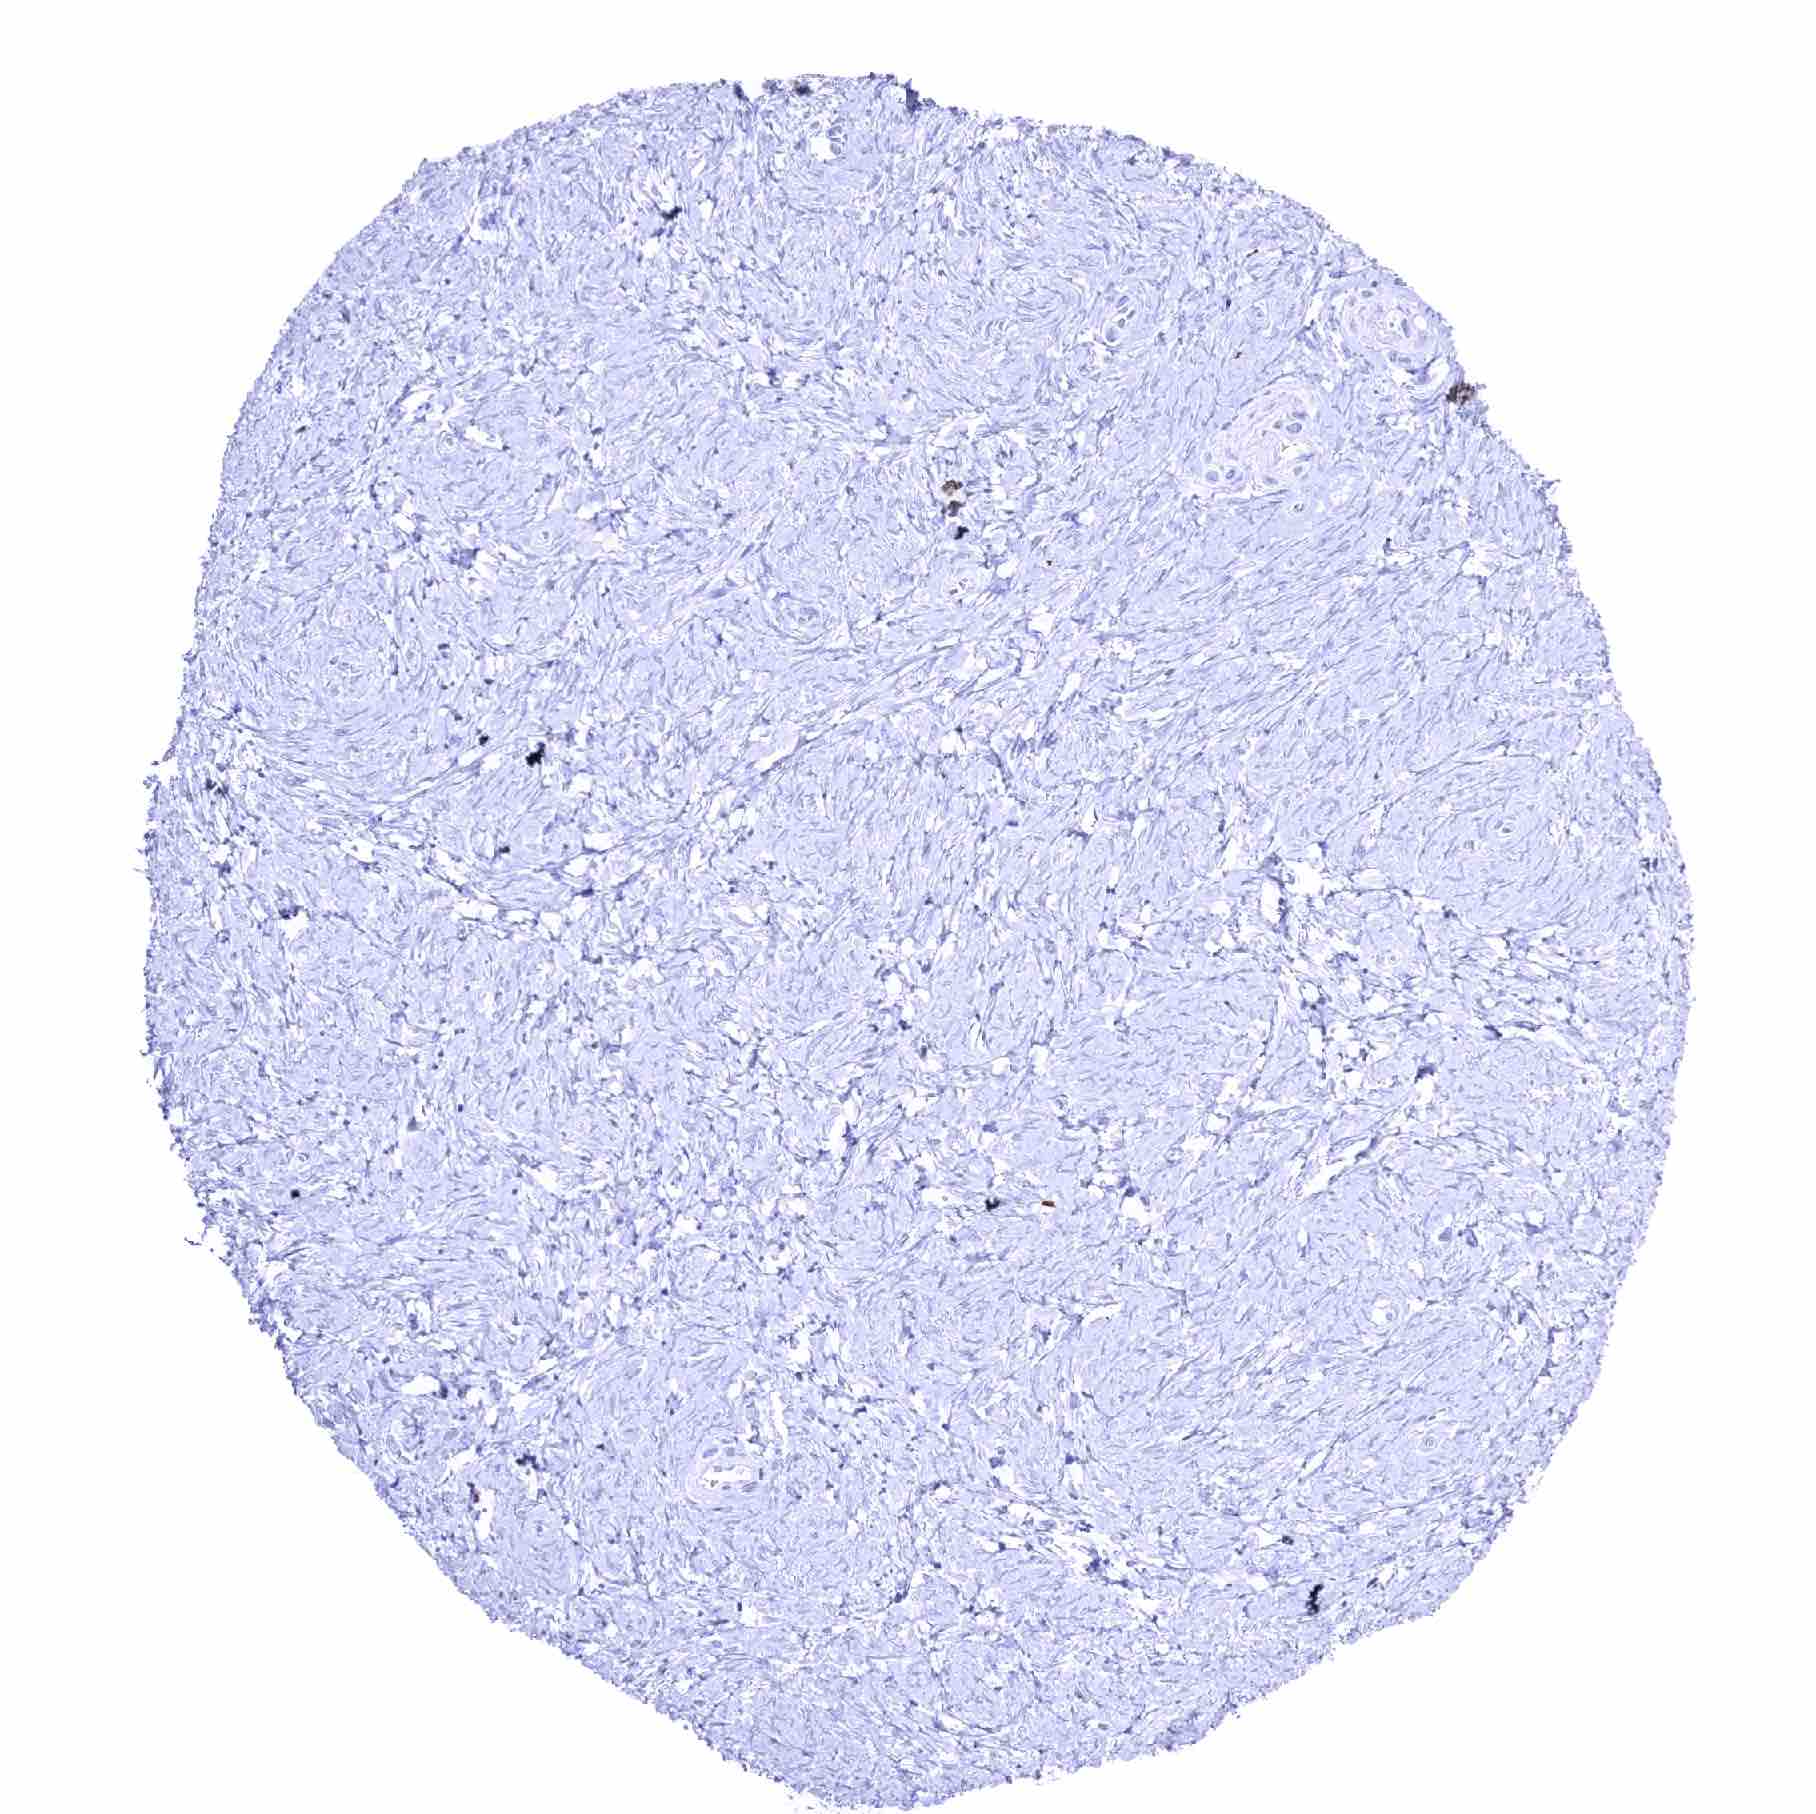

Fat